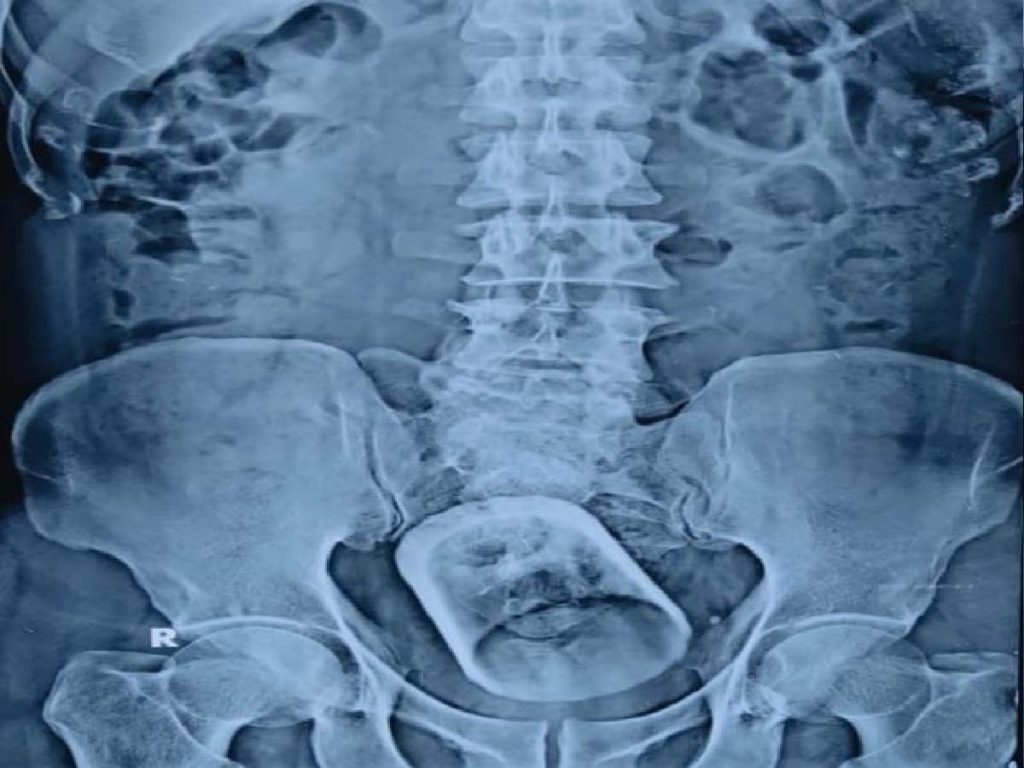

చిన్నపిల్లలు చిన్నచిన్న నాణేలను తెలియకుండా మింగేస్తుంటారు. ఇక కొంతమంది బంగారం ఇతర వస్తువులను మింగేస్తుంటారు. అయితే, బీహార్ చెందిన ఓ వ్యక్తి ఏకంగా చాయ్గ్లాస్ను మింగేశాడు. కడుపు నొప్పి రావడంతో ఆసుపత్రికి తరలించారు. కడుపులో ఏదో వస్తువు ఉందని గమనించిన వైద్యులు ఎండోక్కోపీ విధానం ద్వారా పరీక్షించగా, కడుపులో గ్లాసు ఉన్నట్టు గుర్తించారు. మలద్వారం ద్వారా బయటకు తీసుకురావాలని ప్రయత్నించినా కుదరకపోవడంతో వెంటనే ఆపరేషన్ చేసి గ్లాసును బయటకు తీశారు. అయితే ఆ వస్తువును ఎలా మింగాడు అన్నది వైద్యులకు సైతం అర్థం కాలేదు. గొంతుద్వారా అంతపెద్ద గ్లాస్ వెళ్లదని వైద్యులు చెబుతున్నారు. ఈసంఘటన బీహార్లోని వైశాలీ జిల్లాలోని మహువా ప్రాంతంలో జరిగింది. ప్రస్తుతం బాదితుడి ఆరోగ్యం నిలకడగానే ఉందని వైద్యులు పేర్కొన్నారు.